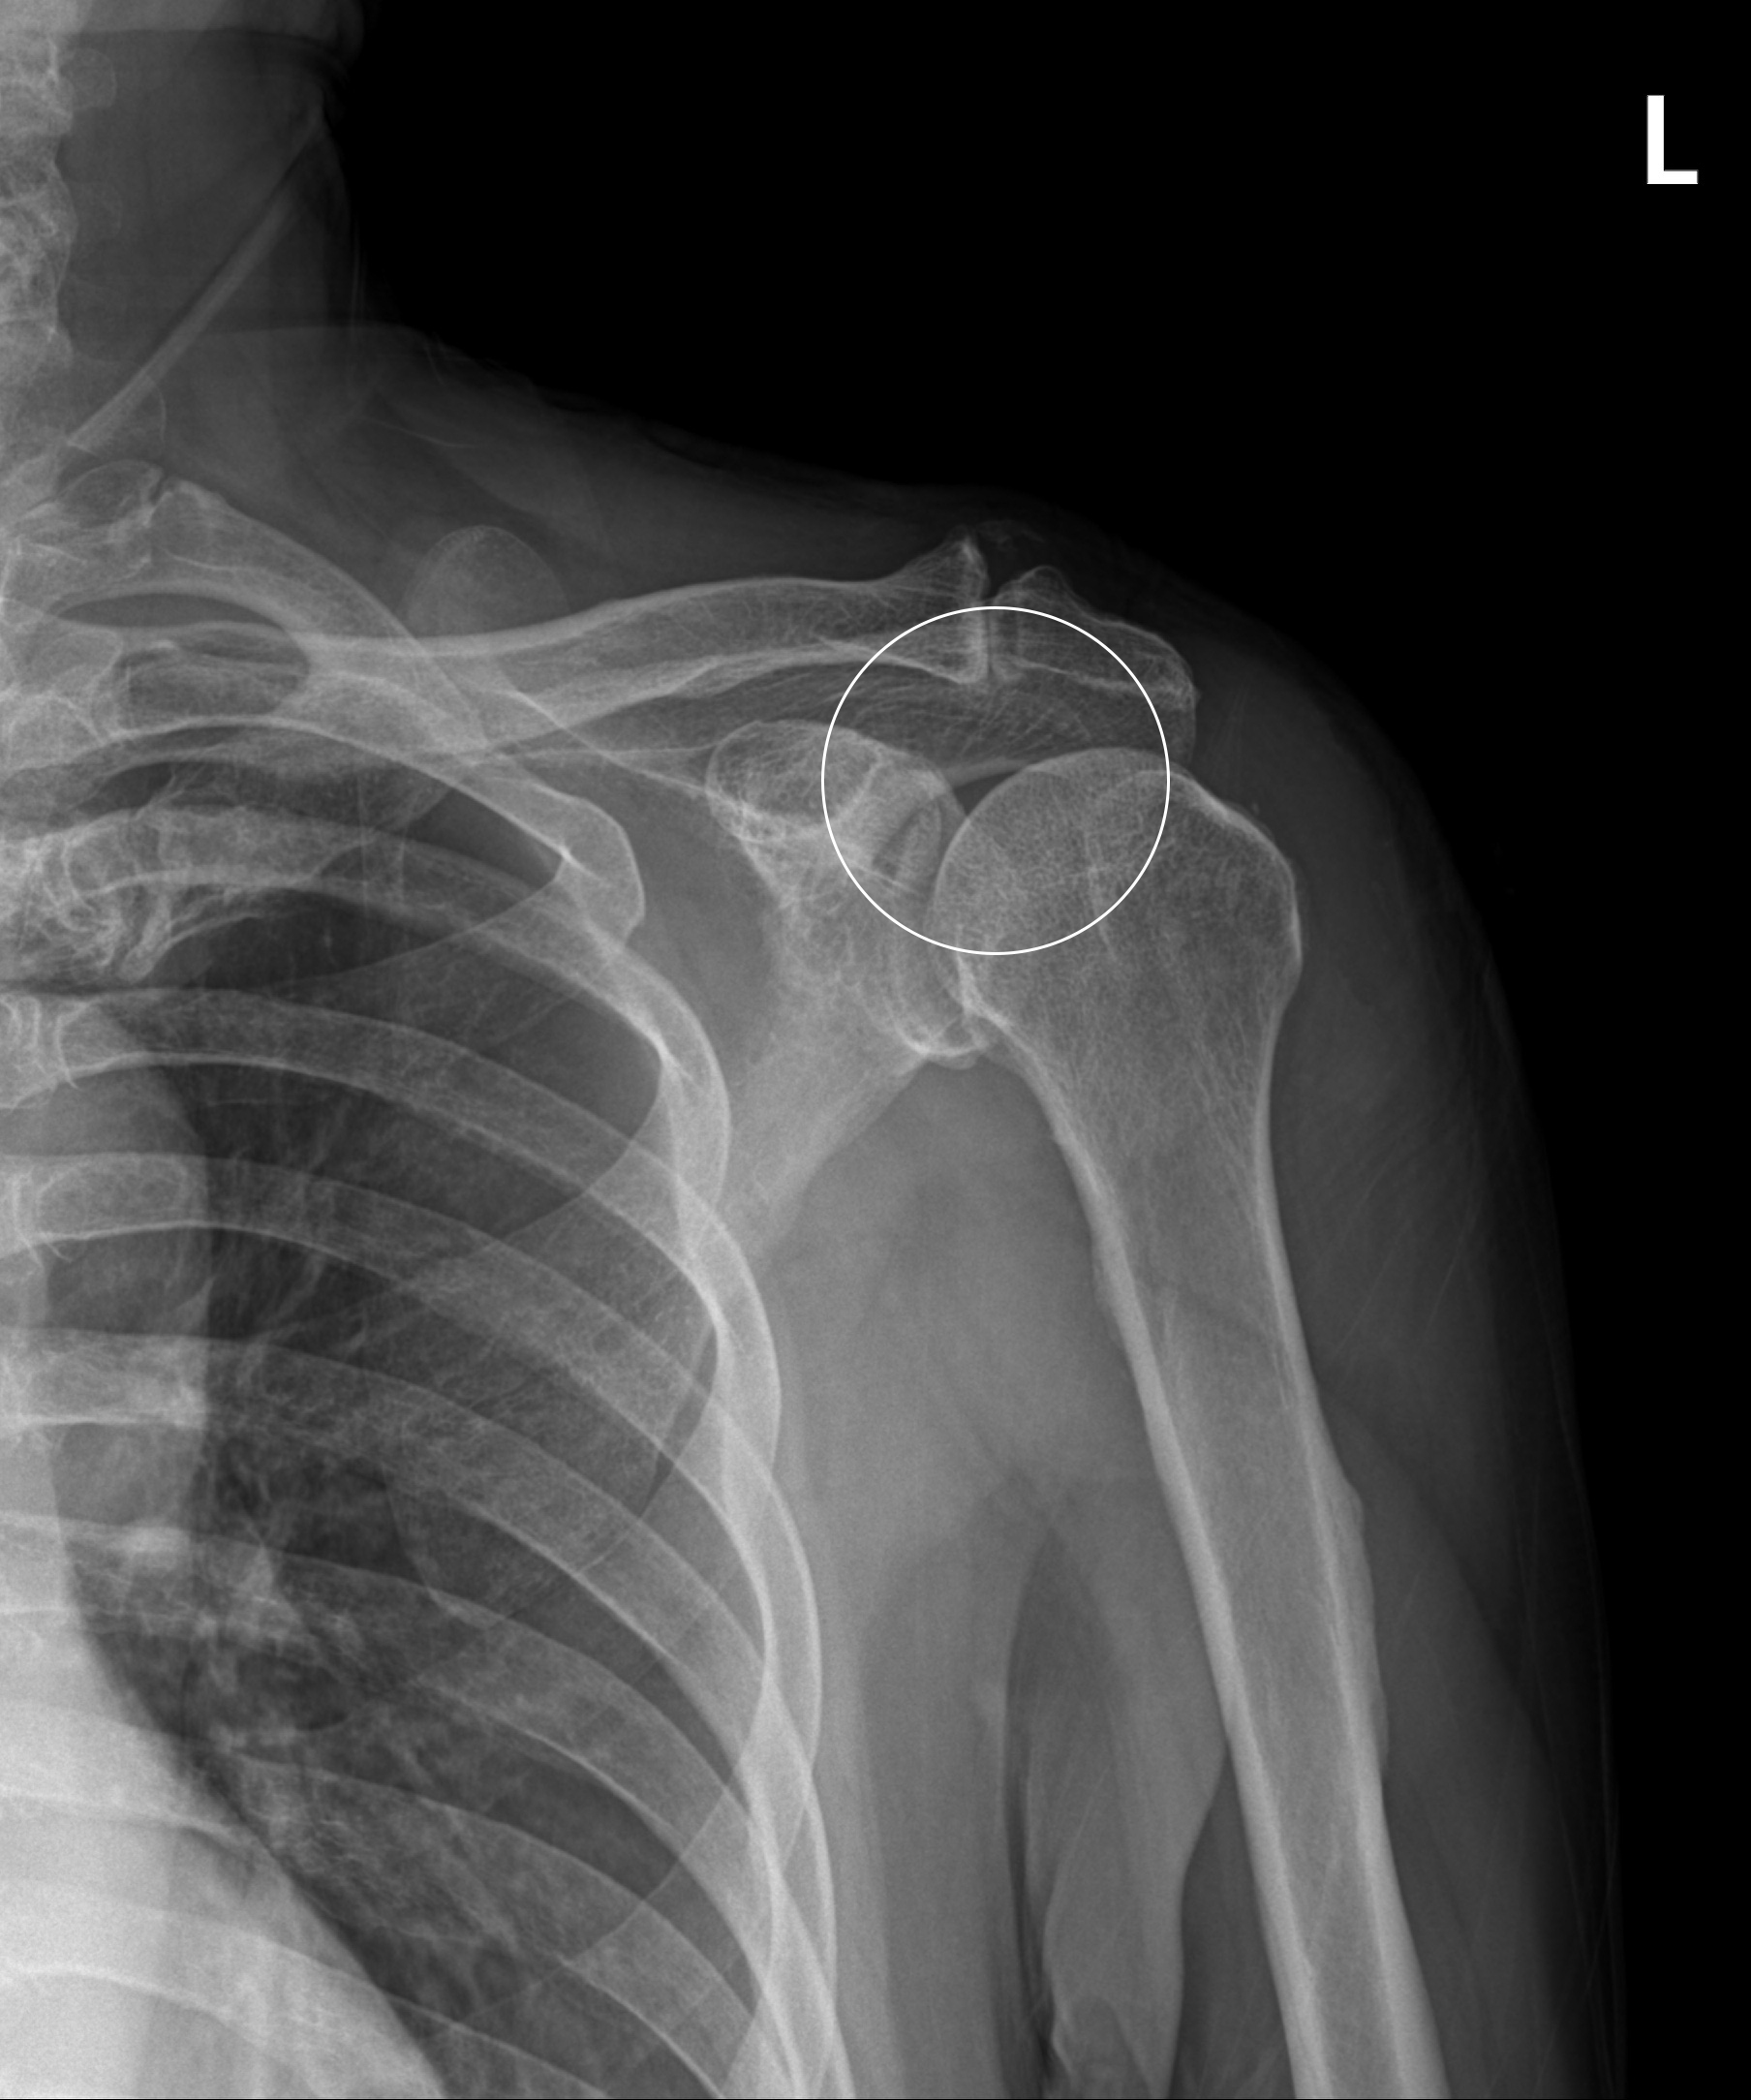

어깨충돌증후군

어깨 견봉과 위팔뼈인 대결절부 사이의 공간이 좁아지면서 뼈와 힘줄 사이에 마찰이 발생하는 질환을 말합니다. 정상 어깨관절에서는 이 공간이 충분하나 어깨를 많이 사용하거나 운동을 무리하게 한 경우 또는 퇴행성 변화 및 뼈의 변형으로 인해 견봉과 어깨 힘줄 사이에 간격이 줄어들어 마찰이 발생하고 힘줄 변성 및 통증이 발생하게 됩니다.

관절내시경을 이용한

견봉성형술 및 회전근개 변연절제술

2022-07-11

ㆍ환자 동의를 받은 자료이며, 이미지 사진은 실물과 다를 수 있습니다.